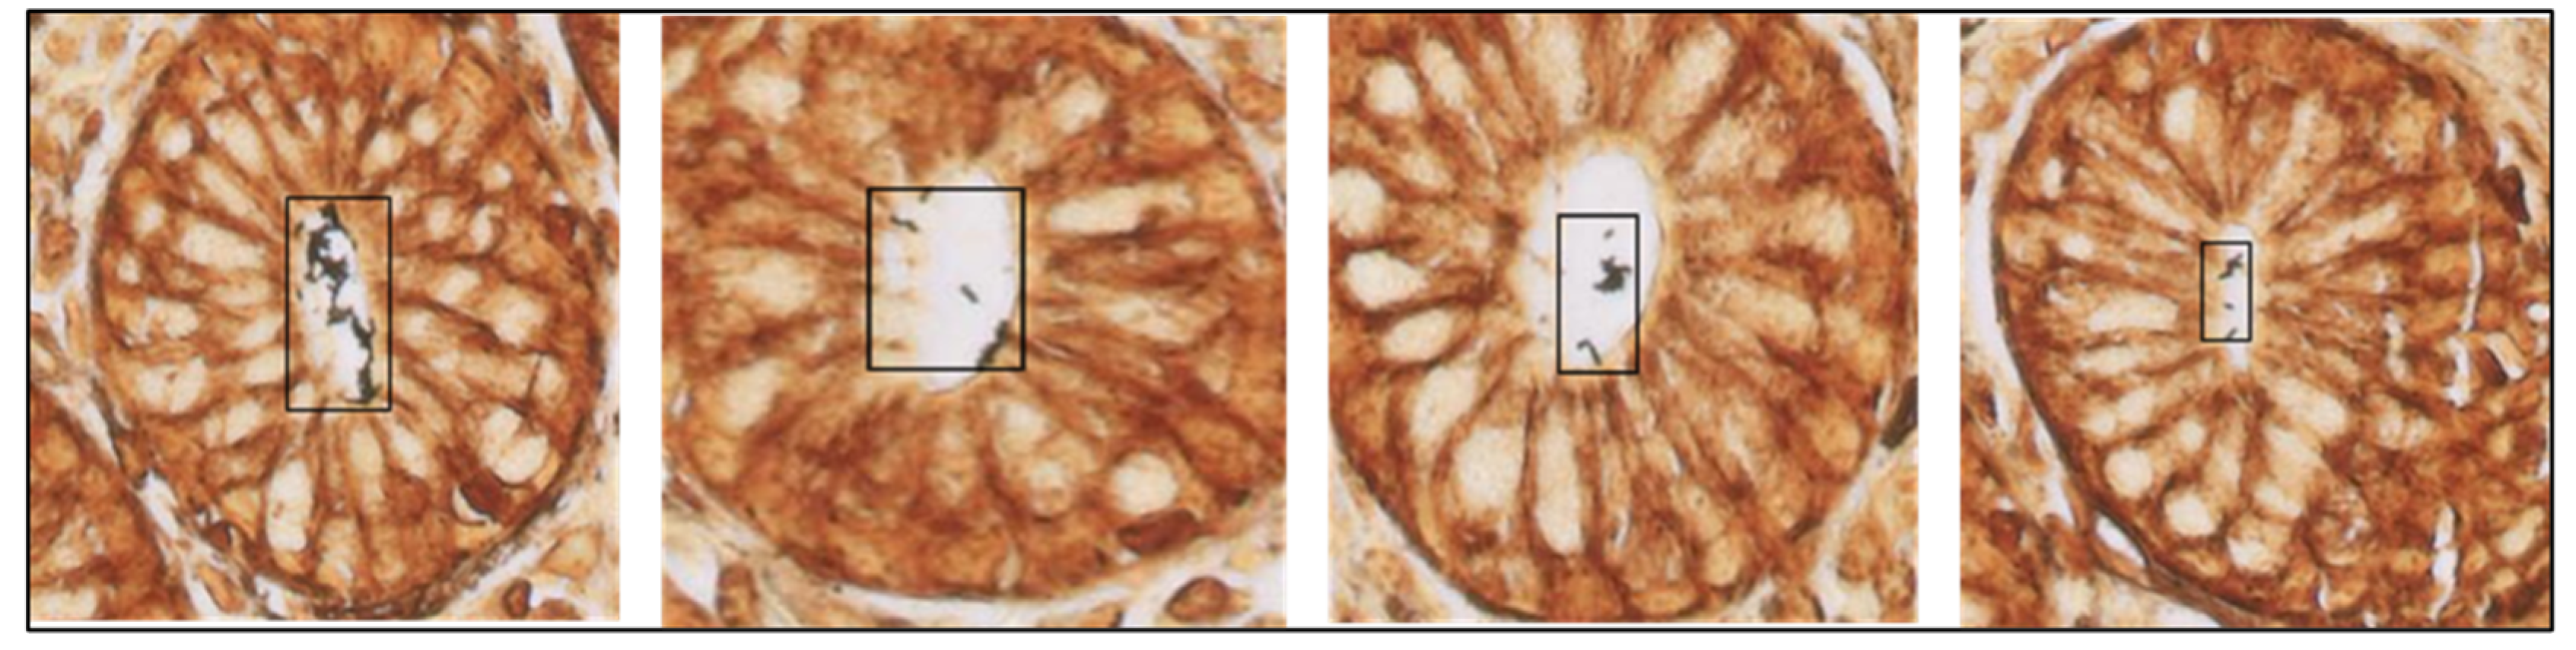

Figure 5.

H. pylori-positive patches were detected by the algorithm on four different Warthin–Starry-stained gastric samples (40× magnification).

Finally, unaided vs. AI-assisted diagnostic turnaround times were measured and recorded for all the participants (Table 3). To assess whether AI assistance was particularly effective in H. pylori-positive or -negative samples, we also recorded turnaround times stratified by H. pylori infection status. For the unaided diagnosis, each participant independently analyzed 60 H. pylori-positive and -negative randomized WSIs; after a waiting time of 60 days, the same 60 images were newly randomized, uploaded to a sample viewer tool, and presented again to the participants for AI-aided diagnosis. This assistance consisted of the detection and identification of H. pylori hot spots by CS-Bacter, which were highlighted by a black box over the image for user verification (Figure 5). The gold standard for this study was established based on the assessment of our reference pathologist, who independently reviewed all cases and determined the presence or absence of H. pylori based on histopathological examination of the samples, serving as the ground truth for our analysis. None of the participants enrolled in the study were involved in the generation of this ground truth, ensuring an unbiased evaluation of unassisted vs. AI-assisted diagnosis.

Histopathological examination remains the gold standard for the diagnosis of H. pylori. The CS-Bacter algorithm was designed and developed to facilitate the work of the pathologist by identifying H. pylori-positive areas on digitalized WS-stained gastric samples, automatically detecting potential H. pylori hot spots so that a swifter, more efficient diagnosis can be made. Identification of these hot-spot areas occurred in two steps: first, the algorithm divided the image into smaller patches and detected the presence of Gram-negative bacteria in the WSI, followed by identification of those bacteria in contact with the gastric epithelial surface (the location of H. pylori) (Figure 5). The algorithm was trained on a set of 2640 samples (184,000 patches), manually annotated by expert pathologists, and validated on a set of 528 WSIs, showing a strong performance (IoU threshold = 0.5, average precision = 0.923, average recall = 0.982). The considerable size of the training dataset allowed for the algorithm to be barely influenced by lower-quality stains or samples.